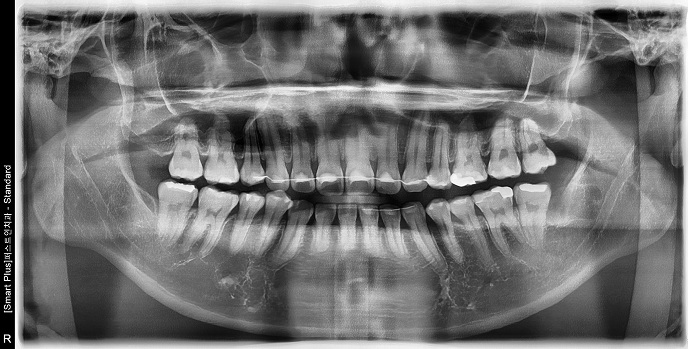

• STEP 02 X-ray 확인

뿌리 형태와 위치, 신경·상악동과의 거리를 파악해 안전한 발치 계획을 세웁니다.